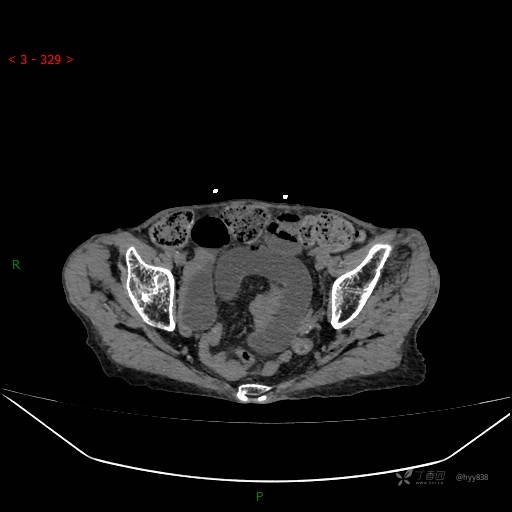

腹部CT平扫